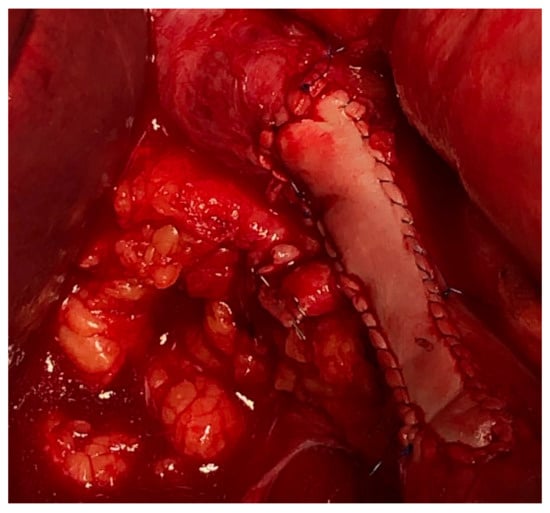

4. Vascular Approach and Types of Reconstruction

Vascular resections can be partial or complete. The type of reconstruction, if any, will be determined by the type of vessel, extent of the tumor infiltration, and patency of vessel at the time of resection. Venous resections can be partial (side-wall resection) as they have greater compliance than arteries due to their thinner smooth muscle layer. Partial venous resections can be performed with a vascular stapler or can be performed sharply with subsequent closure of venotomy with primarily suture venorraphy or a patch using a biologic (e.g., bovine pericardium) or synthetic graft to avoid critical venous narrowing after the tumor has been resected (Figure 3).

Figure 3. IVC partial resection with patch repair.